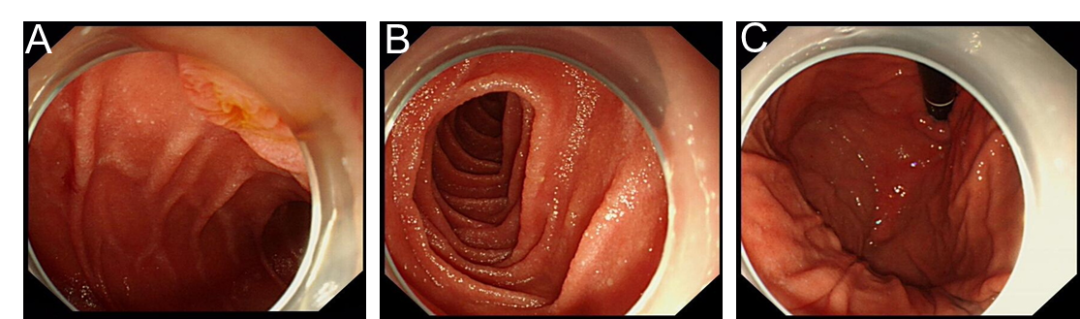

病史摘要:患者为 36 岁男性,主诉持续性腹痛 5 个月,伴黏液血便 1 个月,后进展为不完全性肠梗阻。3 年前确诊急性 B 淋巴细胞白血病,并行异基因造血干细胞移植,移植后发生累及口腔及皮肤的急性移植物抗宿主病,使用环孢素、芦可替尼治疗至腹痛发作。 诊疗过程:实验室检查示 D - 二聚体及超敏 C 反应蛋白升高,其余正常。结肠镜见乙状结肠及直肠黏膜充血等改变,CT